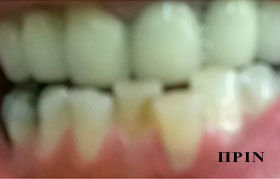

λεύκανση